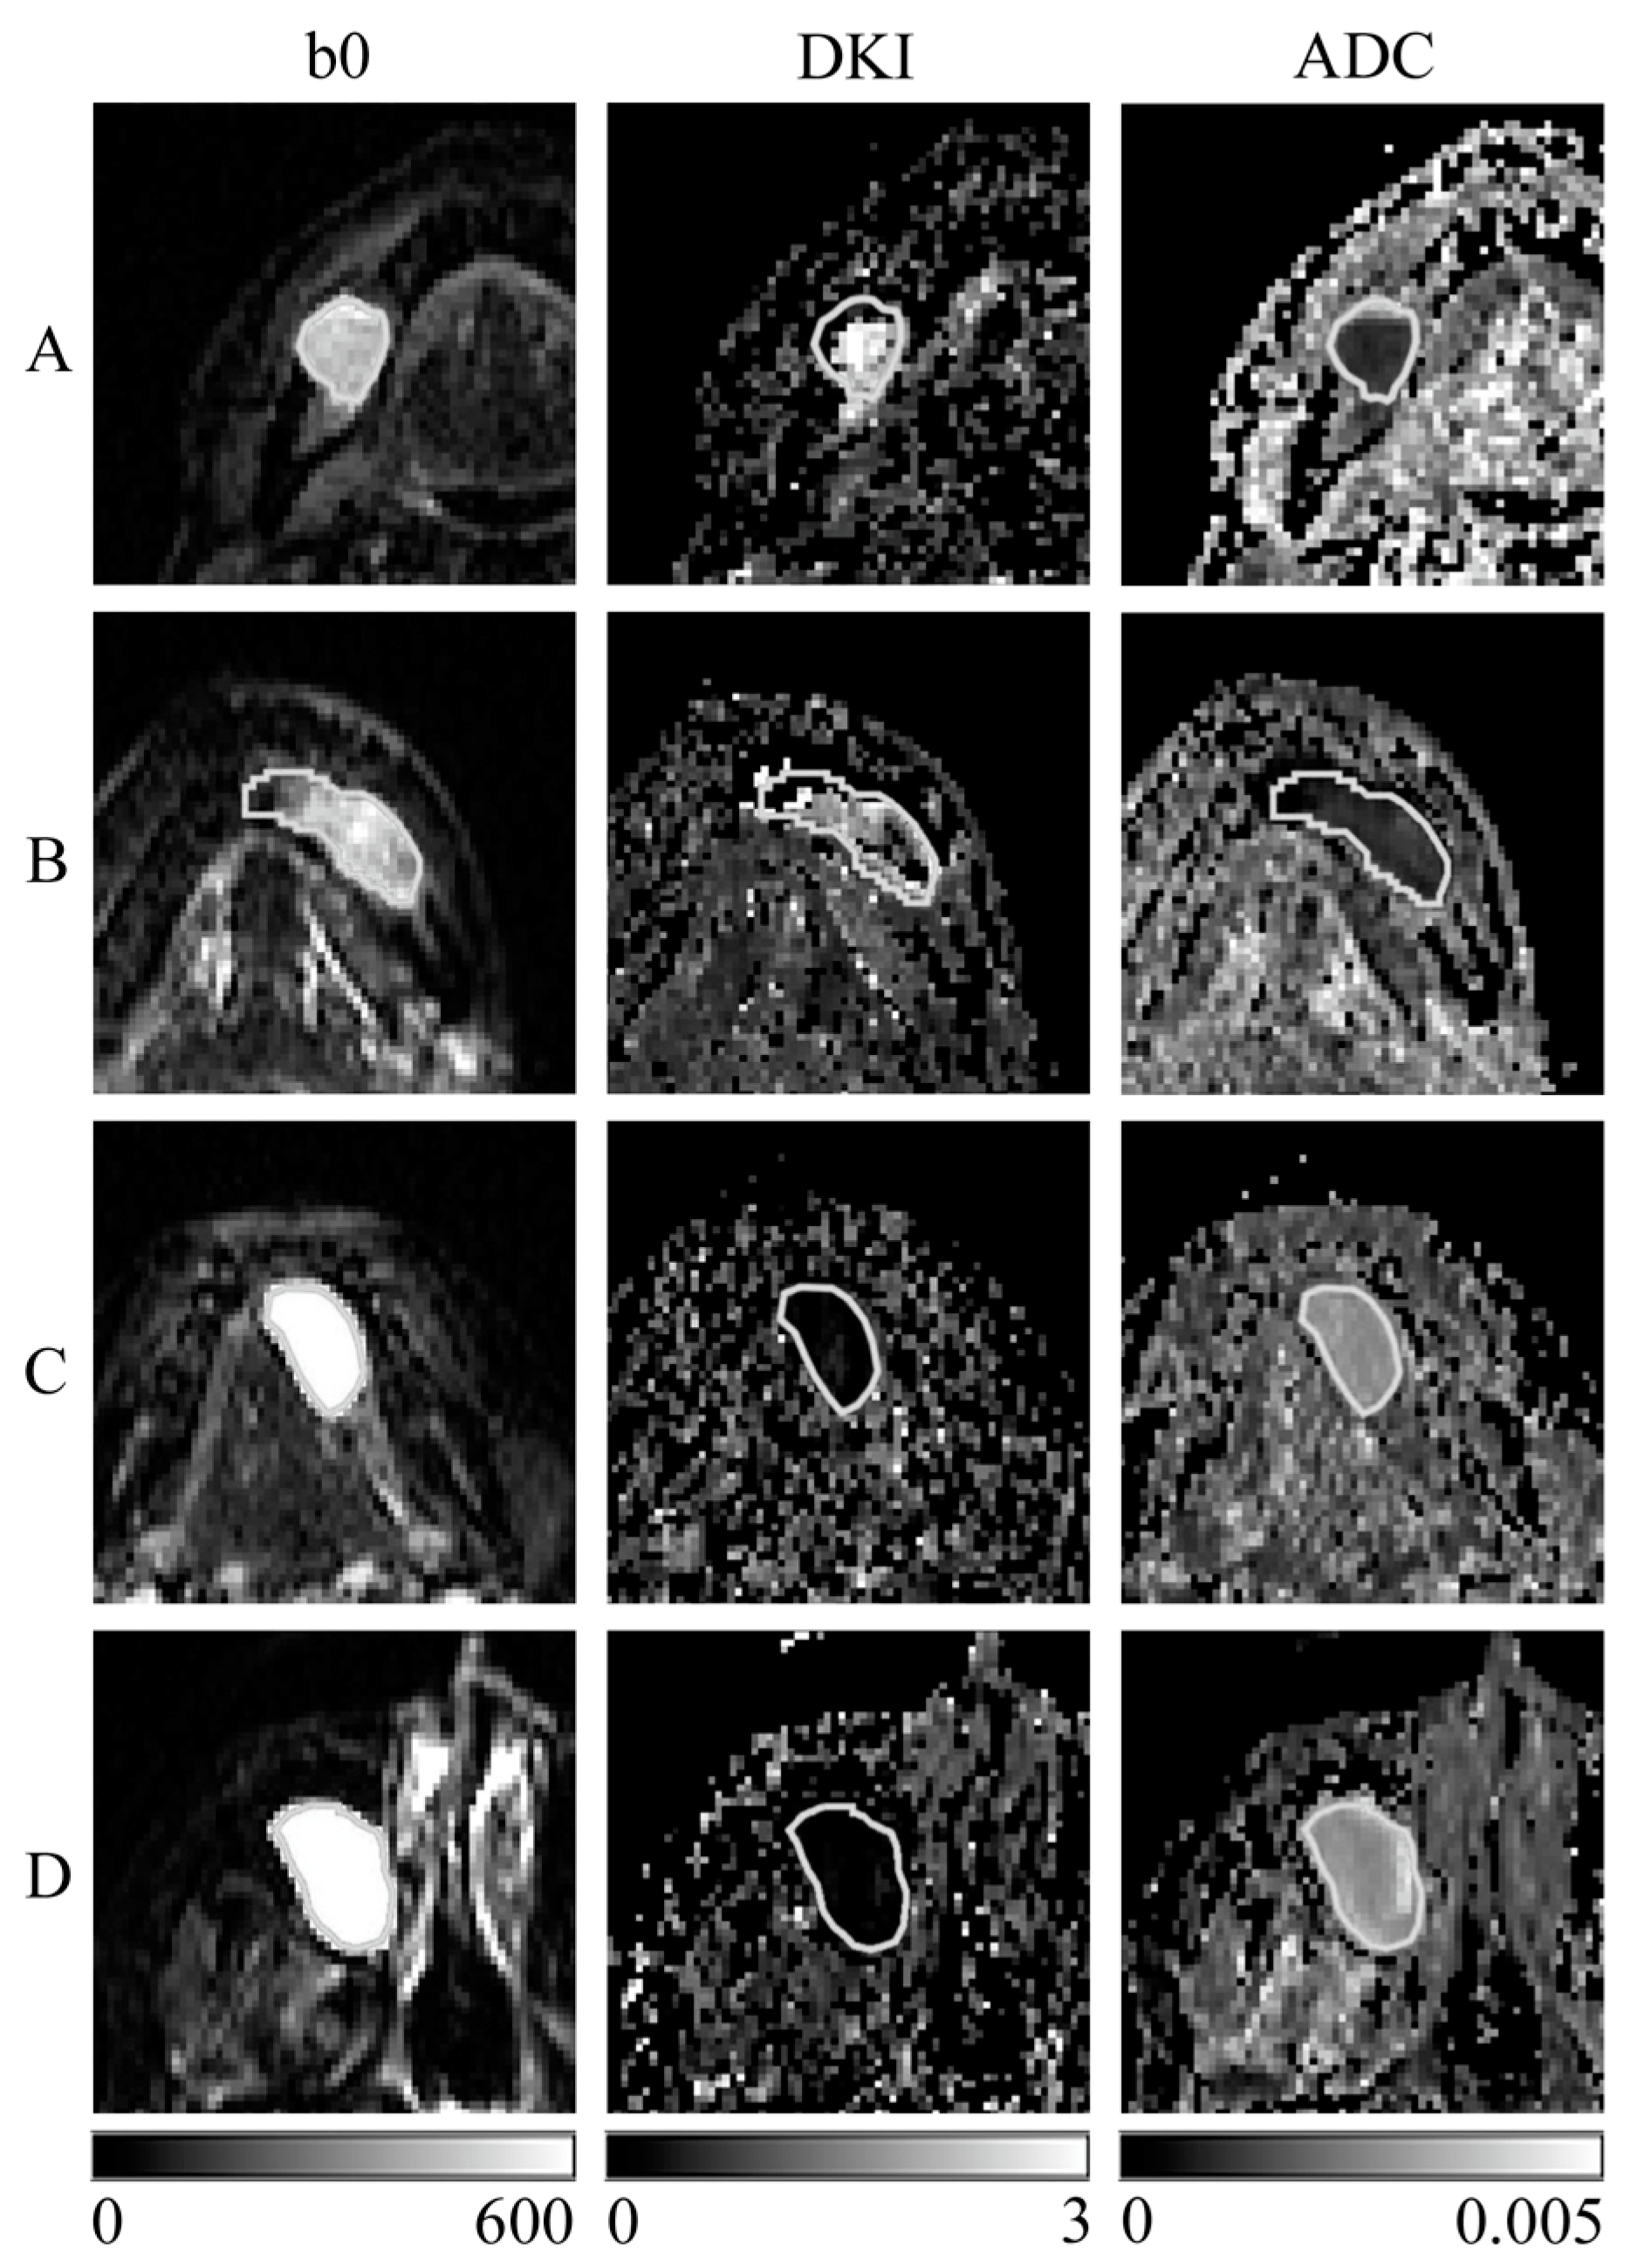

- Kuroda, M.; Konishi, K.; Sugimoto, K.; Yoshimura, Y.; Hamada, K.; Khasawnehc, A.; Barham, M.; Tekiki, N.; Sugianto, I.; Bamgbose, B.O.; et al. Evaluation of fast diffusion kurtosis imaging using new software designed for widespread clinical use. Acta Med. Okayama 2022, 76, 297–305. [Google Scholar] [CrossRef]

- Shimizu, Y.; Kuroda, M.; Nakamitsu, Y.; Al-Hammad, W.E.; Yoshida, S.; Fukumura, Y.; Nakamura, Y.; Kuroda, K.; Kamizaki, R.; Imajoh, S.; et al. Usefulness of simple diffusion kurtosis imaging for head and neck tumors: An early clinical study. Acta Med. Okayama 2023, 77, 273–280. [Google Scholar] [CrossRef]